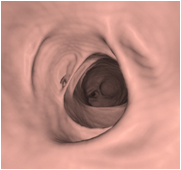

大腸CT(仮想大腸内視鏡)導入

内視鏡を使用せず、検査前に肛門から炭酸ガスを注入し大腸を膨らませた状態でCT撮影(仰向けとうつ伏せ)を行う新しい検査です。得られた画像にコンピューター処理を加え、仮想大腸内視鏡検査として診断を行います。大腸内視鏡検査に比べ比較的、前処置(検査前に大腸内をキレイにする)や検査中の苦痛が少なく、身体に優しい検査です。

[大腸CT検査は以下の方々に適しています]

① ご高齢などが理由でお身体への負担が少ない方がよい方。

② 大腸に狭窄部位があり内視鏡検査が困難な方。

③ 大腸内視鏡検査が苦手な方。